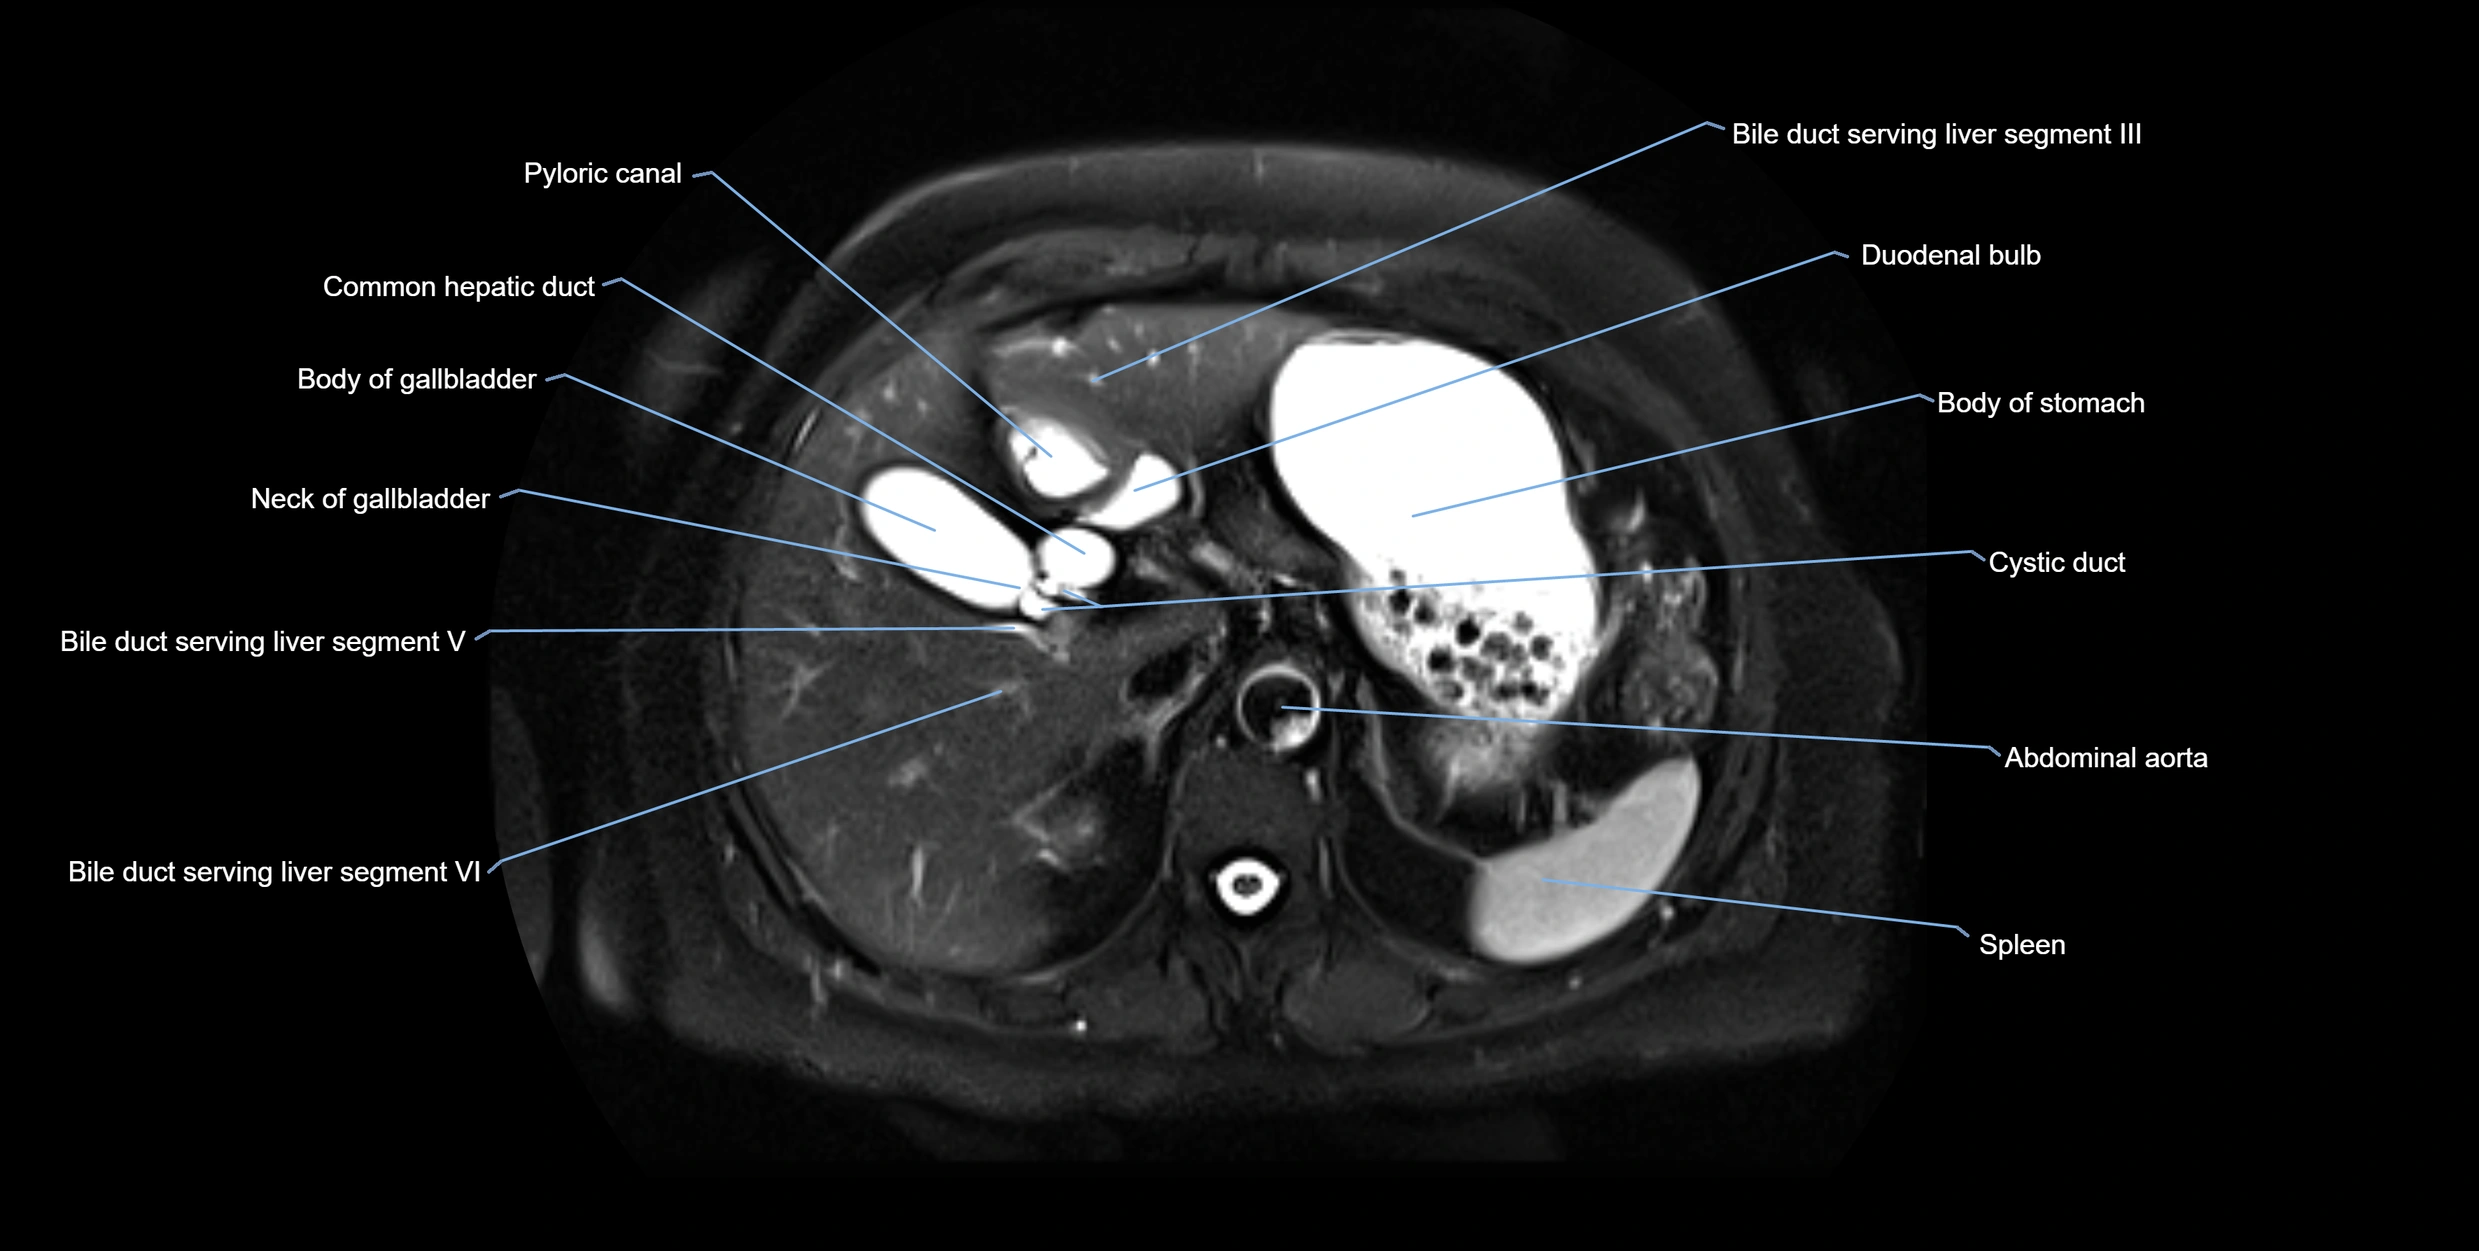

MRI image

image